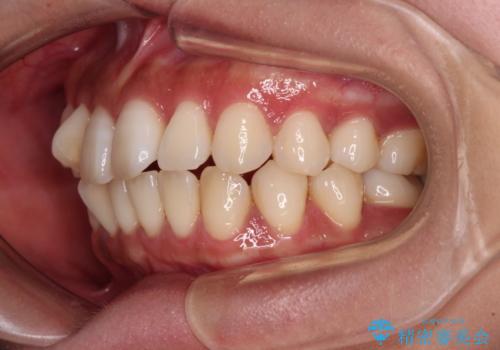

【モニター】上顎前突と奥歯の鋏状咬合 補助装置を用いたインビザライン矯正治療

上顎最後臼歯は極端に外側を向いており、下顎骨に対して上顎骨が前方に位置していたため、補助装置により最後臼歯を一気に内側に引き込むとともに、上顎臼歯を後方移動させ、奥歯の咬み合わせが改善した後に、上下インビザラインにより歯列全体を整えていくこととしました。

奥歯の咬み合わせを事前に望ましい位置に改善したことで、インビザライン単独では改善が最も困難な状況を排除することができ、非常に理想的な仕上がりとなりました。